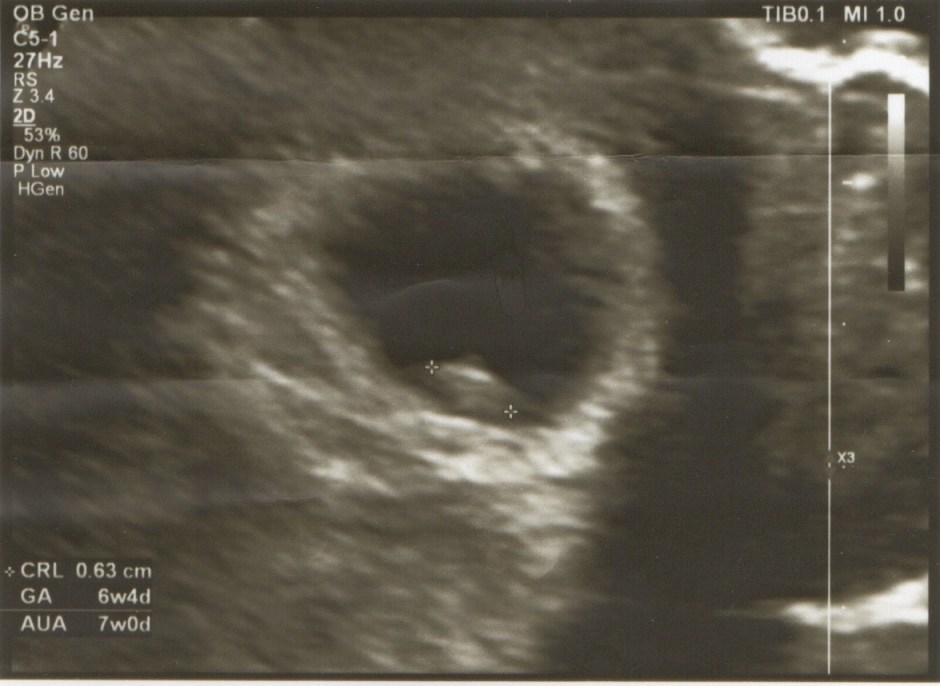

醫生很仔細的幫我們照了腹部超音波,說著床位置跟妊娠囊大小都很正常,一切都很好,不用擔心,量了一下尺寸,沒想到推估是已經7週了,差一點就可以直接拿孕婦加值手冊,可惜下週還要再來一次,不過可以再照一次超音波也是不錯。